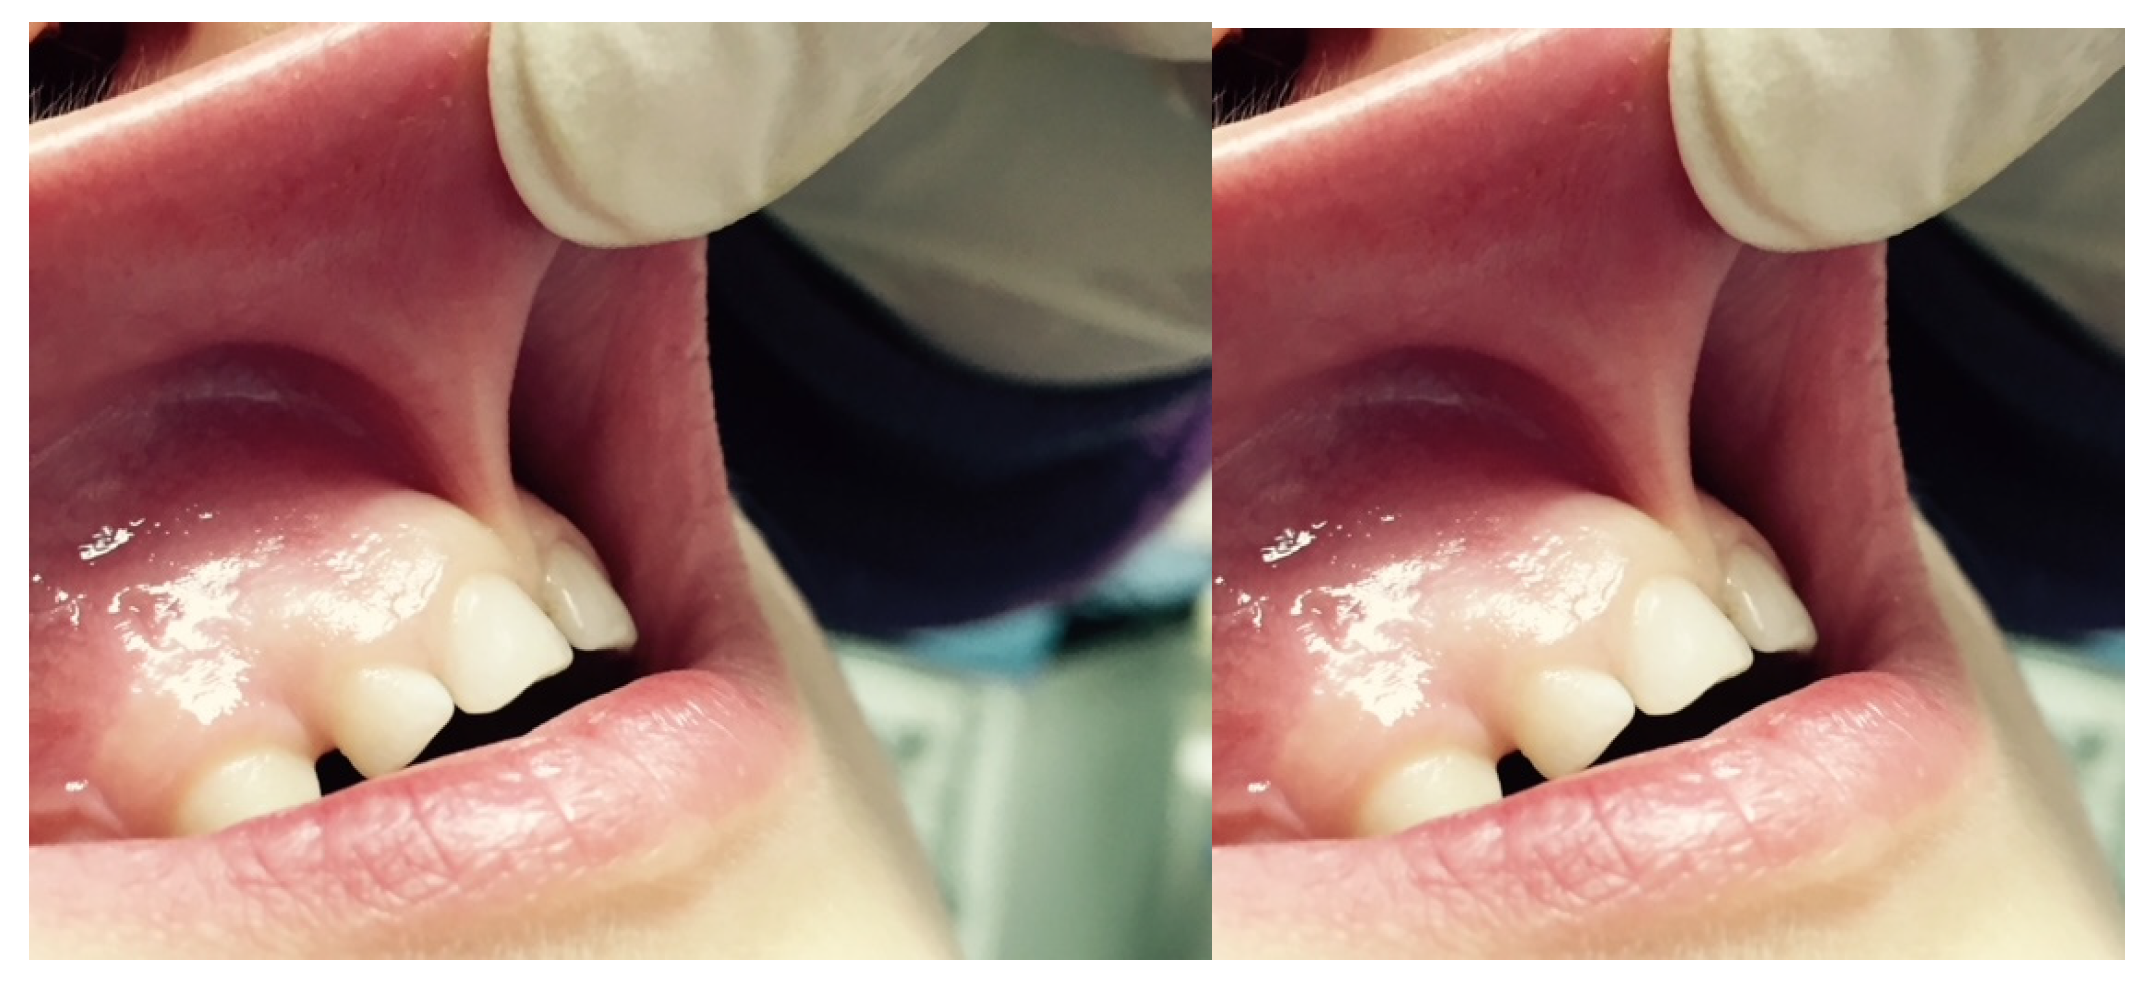

A characteristic of an abnormal frenulum, known as “pull syndrome,” is the ischemization of the palatine papilla and mesial gingival borders of the upper central incisors after traction of the top lip (Figure 1).

Figure 1.

Example of the hypertonic ULF.